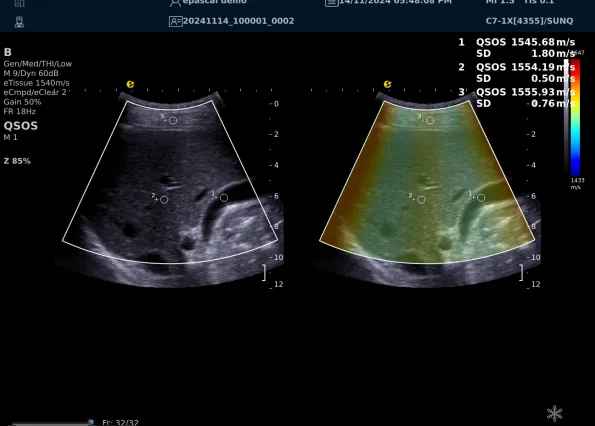

640.jpg123 (2).jpg可以设想,单位时间可发射的脉冲波越多、单位面积可发射的脉冲波越密集,得到的数据结果就越快、越多。也就是说,如果医生希望得到实时、大幅的声速定量图像,就需要超声系统具备“超快速”发射和接收的能力,利来国国际网站医疗(ESI)ePascal东风系列超声平台的200+倍成像速度,成为了这项新技术得以临床应用的重要条件。

以上为应用声速定量成像技术检查肝脏的超声图像,图中在取样框内选择了三个测量区域,得出了各区域内的组织声速值以及声速衰减系数等结果。